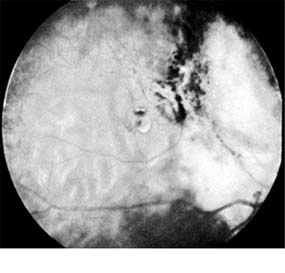

Presumed Ocular Histoplasmosis Syndrome (Figures 10-5, 10-6 and 10-7)

In this disease, serous and hemorrhagic detachments of the macula are associated with multiple peripheral atrophic chorioretinal scars and peripapillary chorioretinal scarring (see Chapter 7). The syndrome usually occurs in healthy patients between the third and sixth decades of life, and the scars are probably caused by an antecedent subclinical systemic infection with Histoplasma capsulatum. The macular detachments are due to subretinal neovascularization, and the visual prognosis depends on the proximity of the neovascular membrane to the center of the fovea. If the membrane extends inside the foveal avascular zone, only 15% of eyes will retain 20/40 vision. A macular scar may change over time, and 10% of patients with normal maculae will develop new atrophic scars in this region. The relative risk of developing macular subretinal neovascularization in the second eye of an affected patient is significant, and these patients should be instructed in the frequent use of the Amsler grid and the importance of prompt examination when changes are detected.

Figure 10-5

Figure 10-5: Presumed ocular histoplasmosis syndrome with active disease (large arrows) and an inactive pigmented macular scar (small arrow). Peripapillary pigmentation (curved arrow) is also present.

Figure 10-6

Figure 10-6: The early fluorescein angiogram shows an inactive hypofluorescent scar (small arrow) and the characteristic lacy hyperfluorescence of subretinal neovascularization (open arrows).

Figure 10-7

Figure 10-7: Late fluorescein leakage from macular subretinal neovascularization in a patient with presumed ocular histoplasmosis syndrome.